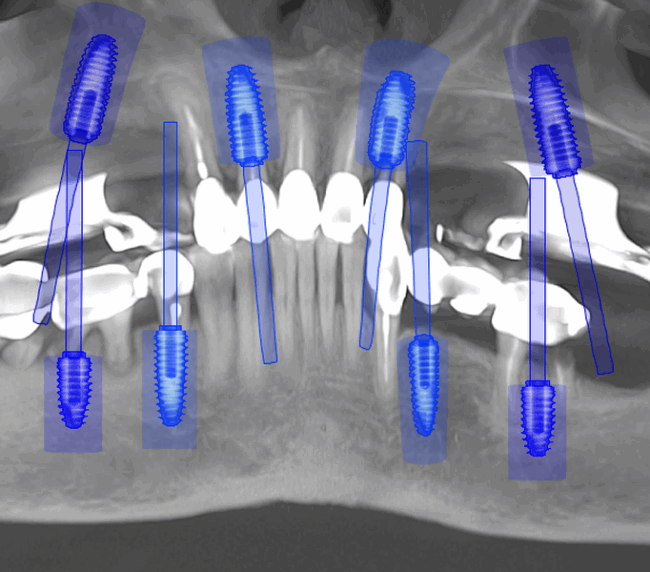

Tomografii (CBCT)

Caz 2

- Investigație imagistică completă, ideal CBCT (computer tomografie);

- Planificare computerizată a intervenției și, dacă este necesar, realizarea ghidului chirurgical;